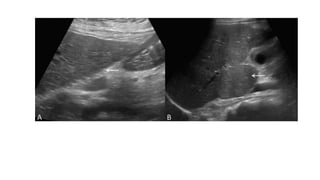

• Imaging Findings

• Ultrasound and Color Doppler-

• The portal vein is replaced by multiple tortuous venous channels at the

porta and peripancreatic regions.

• The pericholecystic vessels also frequently enlarge and become

tortuous.

• The liver surface is smooth and there is no volume redistribution;

however, these can be seen in late stages of disease.

• As PHT develops, there is moderate to gross splenomegaly and

portosystemic collaterals .

• Doppler demonstrates absent flow in the main portal vein and

decreased monophasic flow toward the liver in the portoportal

collaterals